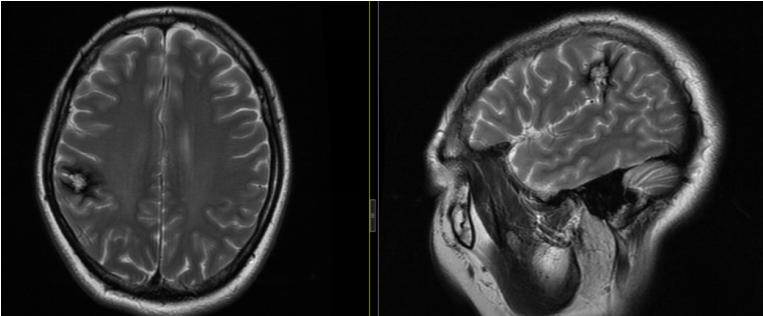

我院神经外六科主任吴杰接诊了患者。结合患者的病史和头部MR检查结果,吴杰认为患者右侧顶叶海绵状血管瘤的诊断基本明确,高度怀疑这是导致患者癫痫症状的罪魁祸首。

▲术前MRI:海绵状血管瘤可能性大